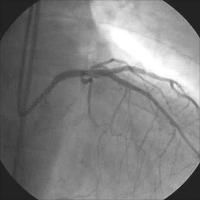

Linke Koronararterie RAO/Kranialprojektion

Abbildung 1: 50 % Ostiumstenose Hauptstamm, Bifurkationsstenose LAD – 1. diagonaler Ast (echte Bifurkationsstenose Typ IV ICPS- Klassifikation ), Y-konfigurierter Abgang des Seitenastes. Kollateralen zur verschlossenen RKA.

Keywords: BifurkationsstenoseKardiologieKoronarangiographieOstiumstenose